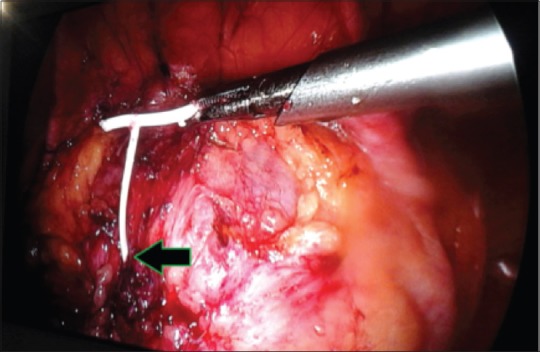

最常用的长期可逆女性避孕方法是宫内节育器(IUCD)。然而,它的使用与文献记载的并发症有关。子宫穿孔,虽然罕见,但可以说是所有这些并发症中最重要的手术。我们报告一例48岁的4+0(4活着)妇女,17年前植入了IUCD,此后有两个孩子,却忘记了她有这个装置。随后,宫内节育器经膀胱穹窿移位至腹膜腔,膀胱内宫内节育器尾线周围形成结石,引起反复尿路感染。这种“衣领钉”效应使得单独的膀胱镜或腹腔镜手术不成功,需要联合手术。本病例报告强调需要联合腹腔镜和膀胱镜的方法在检索的不寻常的表现易位宫内节育器。

The most commonly used long-term reversible female contraception is intrauterine contraceptive device (IUCD). Its use is however associated with documented complications. Uterine perforation, though rare, is arguably the most surgically important of all these complications. We report a case of a 48-year-old para 4+0 (4 alive) woman who had IUCD insertion 17 years earlier and had forgotten she had the device having had two children thereafter. The IUCD was subsequently translocated through the dome of the bladder into the peritoneal cavity with calculus formation around the tail and thread of the IUCD in the urinary bladder causing recurrent urinary tract infection. This "Collar Stud" effect made either cystoscopic or laparoscopic retrieval alone unsuccessful necessitating a combined approach. This case report highlights the need for a combined laparoscopic and cystoscopic approach in the retrieval of the unusual presentation of translocated IUCD.